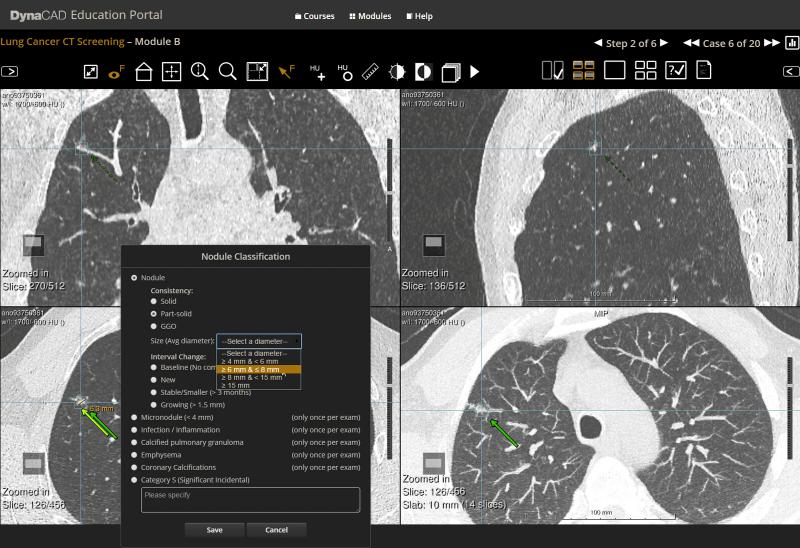

People who have nonsolid lung nodules can be safely monitored with annual low-dose computed tomography (CT) screening, according to a new study published online in the journal Radiology. Researchers said the findings could help spare patients from unnecessary surgery and additional imaging.

An annual exam using a key imaging technology could spare patients with lung nodules from unnecessary tests and surgery, while identifying the cases where the nodules are likely to become cancerous, according to a new study by researchers at Icahn School of Medicine at Mount Sinai (ISMMS) and published online in the journal Radiology.